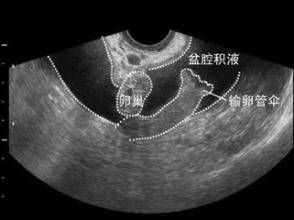

檢查

盆腔積水檢查對識別來自輸卵管、卵巢及腸管粘連形成的包塊或膿腫有85%的準確性。一般用來診斷較為嚴重的盆腔炎。